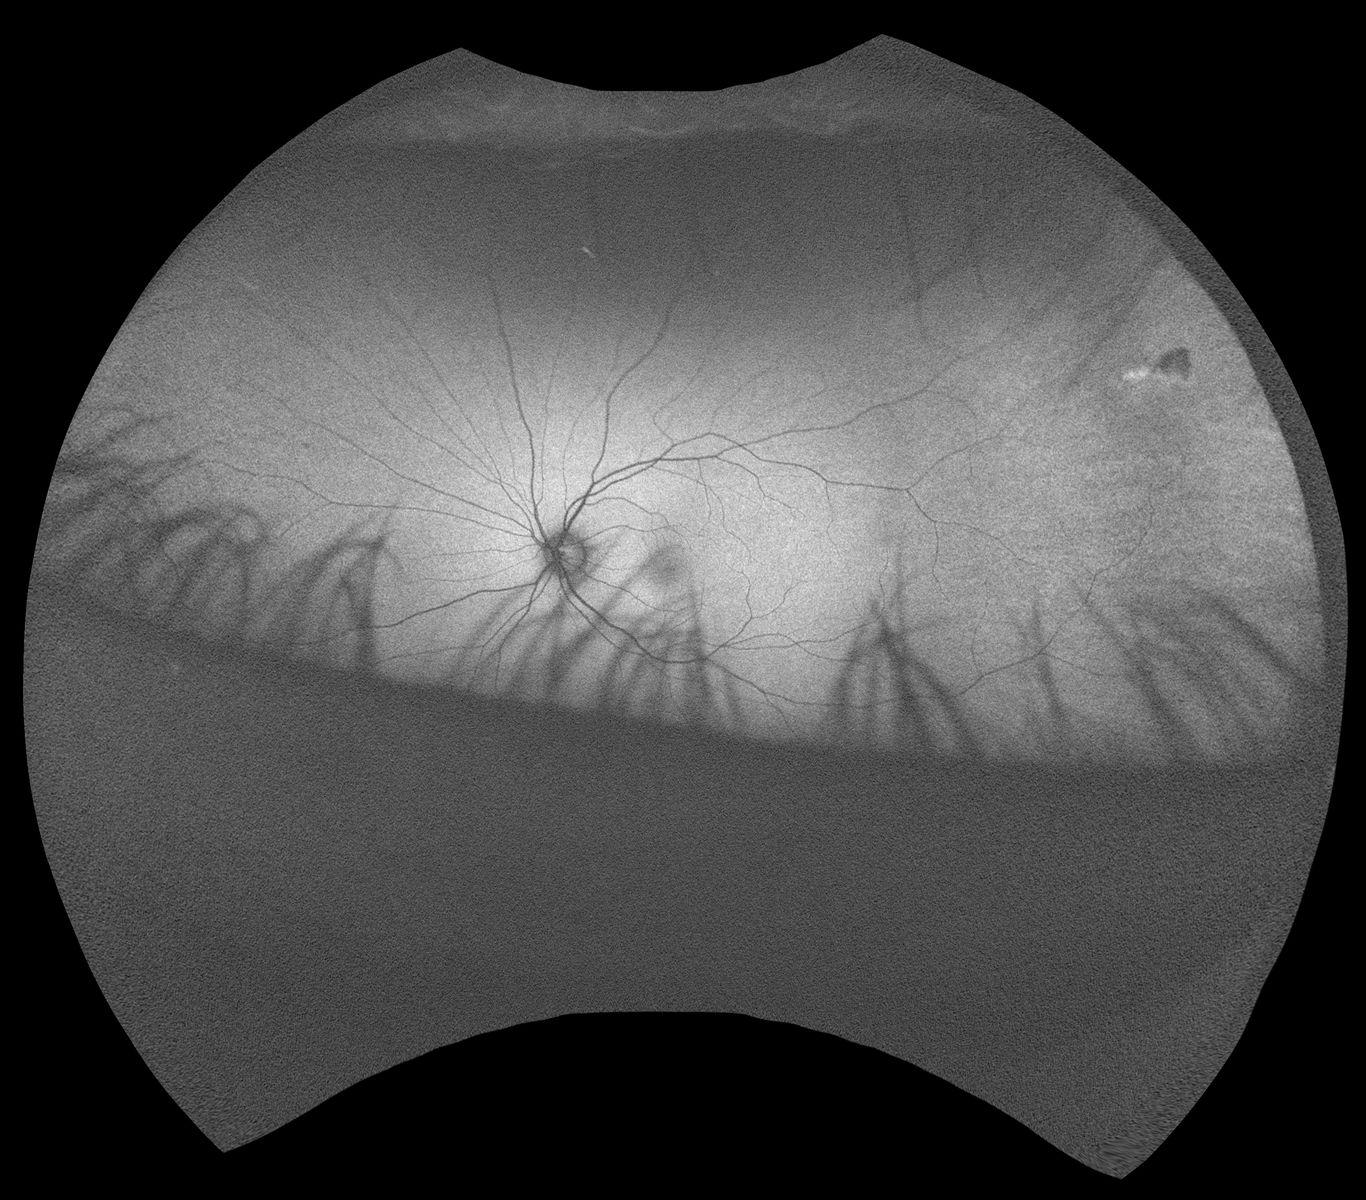

July 6th OCT scan (PDF) ----- fundus (back of retina) photos - July 6th right - OD / July 6th left - OS.

Retina photos by Canon CR-2.

Optomap photos:

Right Eye OD - Black & White / Color

--

Left Eye OS - Black & White / Color

Optomap provides a wider field of view of retinal health. You can see in the left images, upper right, there is a an aberration

/ spot. This is a small dark pigmented spot on the white part of my eye, clearly visible in the mirror. I don't know how long it has been there or why it is there.

Contact lens use? The optometrist said it was nothing to be concerned about. Which is great, but it must affect my vision in

some way. Perhaps in time it will go away. It's a blockage. Like a benign mole on my skin.